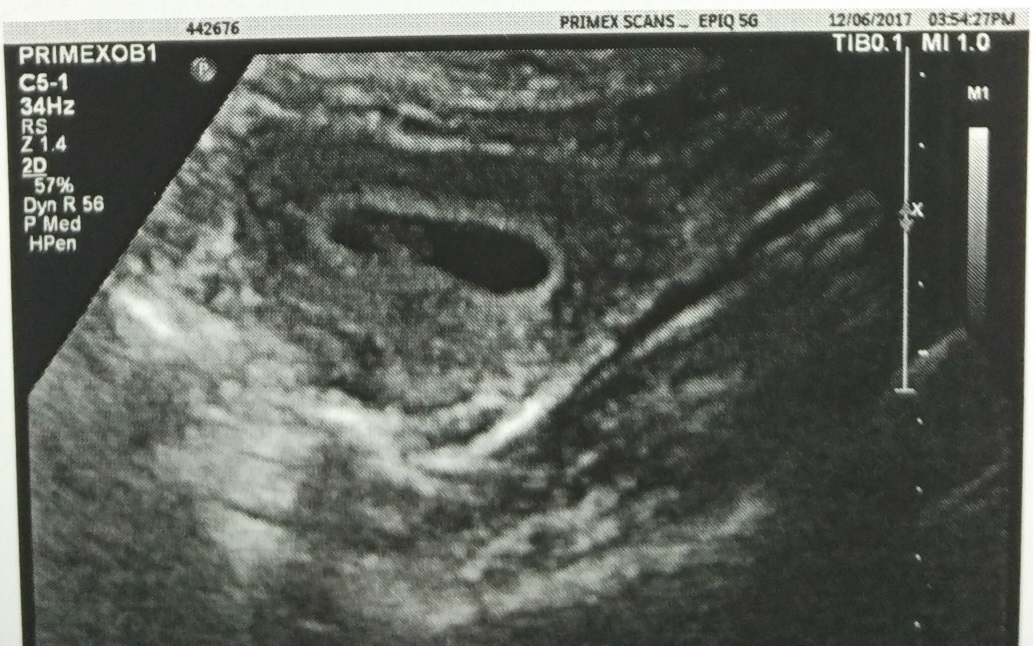

Recently got my ultrasound done (abdominal) at 6w + 6d

Would love to get your guesses on what you think the Ramzi theory suggests - Boy or Girl?

Attachment 36690